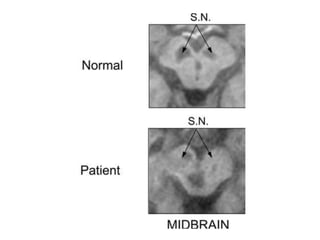

Substantia nigra

• Pigmented layer- melanin granules

• Dorsal to peduncles and ventral to the red

nucleus .

• Composed zona compacta and zona reticulata

• The dopaminergic neurons of pars compacta

mainly deals with motor control

Substantia nigra • Pigmentedlayer- melanin granules • Dorsal to peduncles and ventral to the red nucleus . • Composed zona compacta and zona reticulata • The GABAergic neurons in the pars reticulata convey the final processed signals of the basal ganglia to the thalamus and superior colliculus. • The dopaminergic neurons of pars compacta mainly deals with motor control